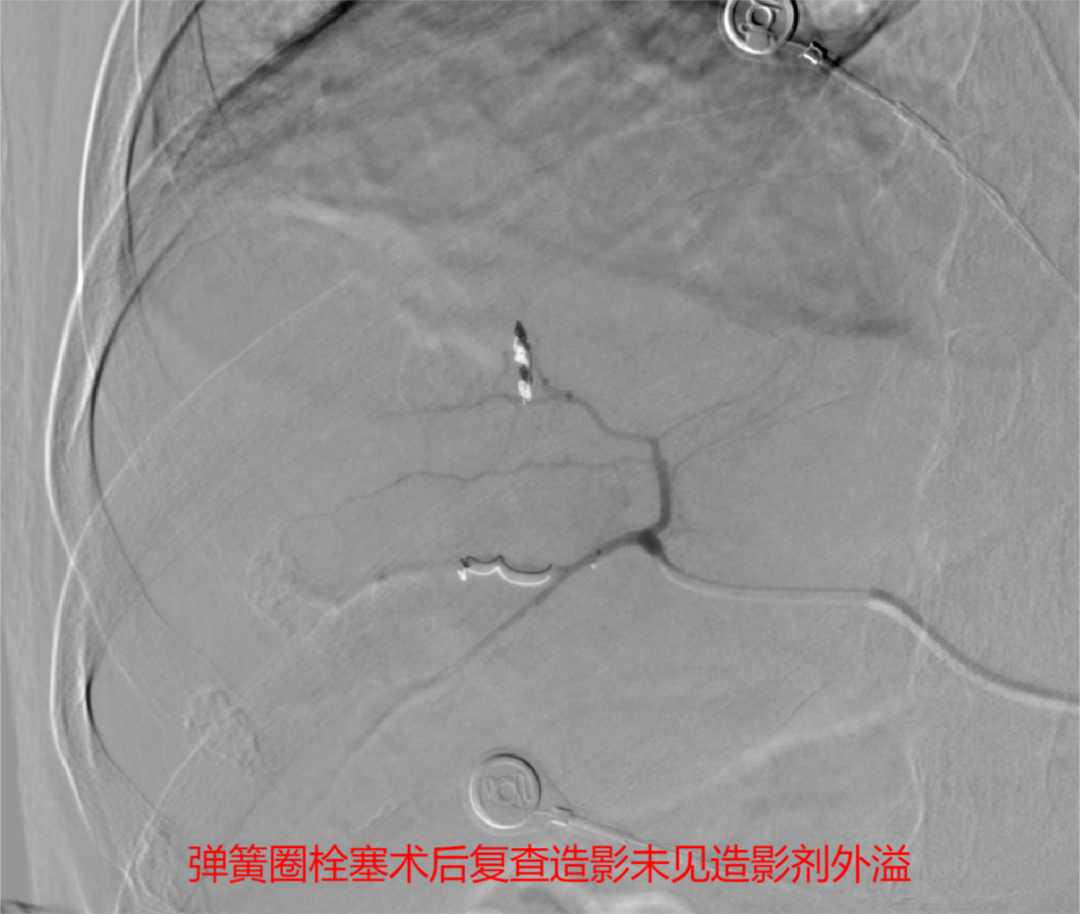

(2)动脉栓塞治疗:①肝损伤部位和拟栓塞的靶血管确定后,超选择性插入相关动脉主干近端,将明胶海绵根据需要剪成粗细不同的颗粒[直径1mmX(1~3mm)]或条块(lmm lmmX5mm),装入混有造影剂及庆大霉素的注射器内并摇匀,在透视监控下缓慢、少量、分次注入损伤血管,当血管血流明显缓慢或铸形,提示出血动脉已闭塞,再造影复查见造影剂外溢消失。

肝脏破裂介入治疗无需全麻,仅通过约1毫米的血管穿刺点进行血管内操作,在DSA下寻找出血点,用栓塞材料“堵”住止血点即可,可在短时间内达到快速止血、抢救病人生命的同时,大大减少血液制品的需求。这种新型的微创介入手术既可以及时抢救生命,又可以大大降低手术风险,减少并发症。时间就是生命,在征得患方同意后,介入团队迅速为患者实施手术抢救。近一个小时的手术,精准地将栓塞材料堵住出血点,成功挽救了患者的生命,提高了患者的生存质量,为患者的后续治疗赢得了机会。